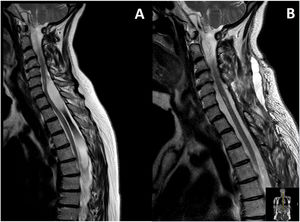

A spinal cord MRI scan (Fig. 1) revealed an intradural extramedullary lesion, with 2 cysts (one at C6-T2 and the other at T3-T6) connected by a more solid band. Compressive myelopathy was observed at the C6 level.

Given these clinical and radiological findings, we indicated surgical treatment. The patient underwent C6-T6 laminoplasty, with complete resection of the mass (Fig. 2). The patient progressed favourably in the postoperative period.